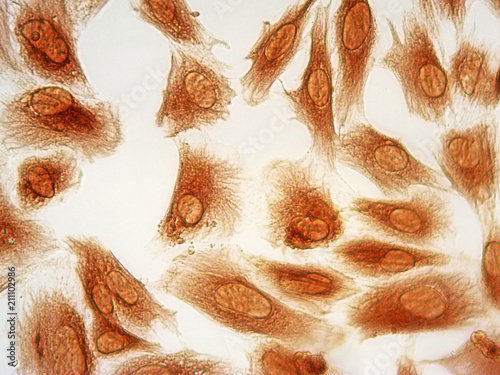

Mikrofotografi - Plakater, Poster, Billeder på lærred